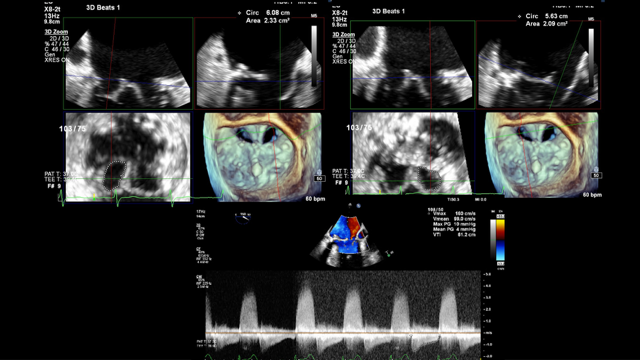

Transthoracic echocardiogram showed severe MR and transesophageal echocardiogram (TEE) showed the Alfieri stitch located at A2/P2 with the tip of the anterior mitral valve leaflet sutured to the ventricular side of the posterior annulus. The origin of the MR was just lateral to the stitch with the Coandă effect into the left atrium; the Coandă effect refers to the wrapping of the eccentric mitral regurgitant jet around the atrial wall by color Doppler (Figure 1). Due to the complicated repair and residual leaflet billowing, determination of the regurgitant jet origin by 2-dimensional TEE was challenging. Multiplanar reconstruction (MPR) of the 3-dimensional (3D) TEE images was used to sweep through the valve, measure leaflet lengths at specific valve segments, and confirm the origin of the MR jet in the challenging post-repair valve anatomy (Figure 2). The mitral valve area (4.0 cm2) was also directly measured using MPR (Figure 3). The patient was determined to be high surgical risk for redo mitral valve surgery (STS score 16.8%) and was referred for mitral edge-to-edge repair.